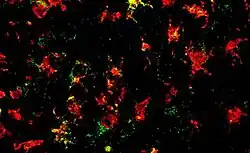

Inflammation study at the University of Queensland

The inflammasome study conducted at the University of Queensland produced a promising new therapy to stop Parkinson's disease progressing through counteracting brain inflammation caused by immune cells.[28] The study primarily targeting ways to counteract immune cells, specifically the microglia which is highly activated in patients with Parkinson's disease by NLRP3 inflammasome. The NLRP3 inflammasome reacts to synuclein containing protein clumps by increasing inflammatory signals which contributes to the depletion of dopamine producing cells within the brain.[29] Whilst, recruiting more pathological proteins to create an intense cycle of neuroinflammation and a synuclein buildup within the brain.[29] The study found that a small molecule MCC950 administered orally once a day, stopped the development of Parkinson's disease in several animal models.[30] It was found to block NLRP3 activation within the brain and prevent both the loss of dopamine producing brain cells and neuroinflammation, resulting in significantly improved motor function - the leading symptom of parkinson's disease.[30] UQ Bioscience researcher Professor Matt Cooper stated that the "MCC950 molecule effectively 'cooled the brains on fire', turning down microglial inflammatory activity, and allowing neurons to function normally."[31]

Currently, there are no medications on the market that prevent brain cell loss in Parkinson's patients. Current therapies focus on managing symptoms rather than halting the progression of the degenerative disease.[31] The promising results from this study validate a promising new target for Parkinson's researcher's and therapeutics to substantiate a potential drug to stop the progression of Parkinson's disease.[32] The drug is now being commercialised for clinical trials by inflamzone,[31] a pioneering biotech company that develops several small molecule drugs that inhibit harmful inflammation within the brain.[33] With the success and extensive research studies taken place to ensure the drug is safe, tolerable and efficacious, human trials of the drug is now attainable.[34] Phase 1 of the clinical trials on healthy volunteers is expected to start in 2019, with phase 2 trials on Parkinson's patient's predicted to take place in 2020 dependent on the results of Phase 1.[31]